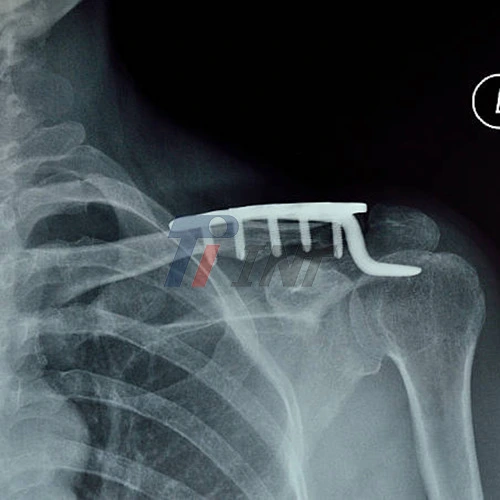

With advancements in medical technology and surgical techniques, the use of internal fixation devices has become increasingly prevalent. Among these, titanium plate for collar bone has gained significant traction due to their unique properties and excellent clinical outcomes.

- Plate Positioning: The titanium plate is carefully positioned along the superior aspect of the clavicle. This placement provides maximum stability while minimizing the risk of hardware prominence or soft tissue irritation.

- Screw Fixation: High-quality titanium screws are used to secure the plate to the bone. The number and configuration of screws depend on the fracture pattern and plate design.